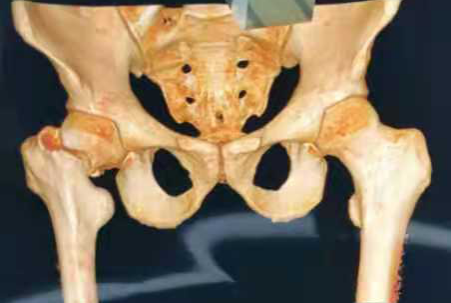

图1 股骨颈骨折Pauwels分型